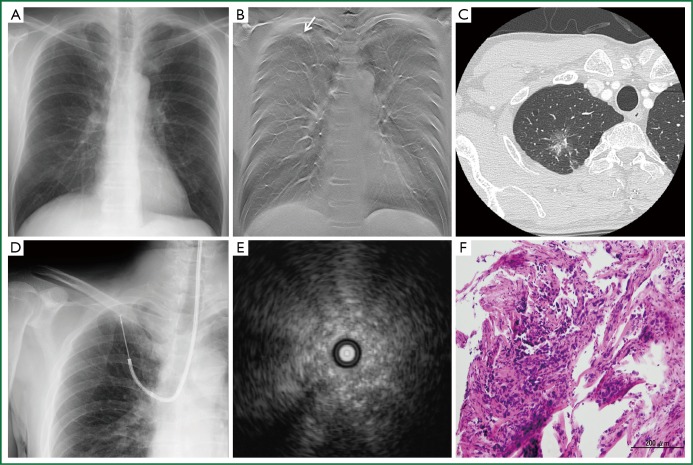

A representative case is shown in Figure 1. A 59-year-old man with a chest CT showing a mixed GGO measuring 24 mm in the major axis in the right S1a was admitted to our hospital. Note that the GGO was not seen on plain radiography (Figure 1A). Prior to bronchoscopy, tomosynthesis images were prepared to map the location of the target site in the coronal plane (Figure 1B). The endobronchial route was planned by reviewing HRCT images (Figure 1C). The EBUS probe was advanced into the B1ai bronchus and manipulated under fluoroscopy guidance (Figure 1D) towards the area indicated by the previously prepared tomosynthesis image. EBUS scanning demonstrated a pattern of low-echoic lesion with hyperechoic dots and linear arcs without vessels (Figure 1E). Histopathological specimen from the TBB showed cuboidal tumor cells lining the entrapped alveolar space.

A representative case of guided bronchoscopy in a 59-year-old man with mixed ground glass opacity (GGO) in right upper lobe. (A) No abnormal shadow on chest radiograph; (B) Chest tomosynthesis showing a GGO lesion in the right upper lung field clearly (arrow); (C) High resolution CT scan shows a 24 mm mixed GGO in right S1a; (D) Real-time fluoroscopy imaging during EBUS-GS procedure; (E) The EBUS image revealed a pattern of low-echoic lesion with hyperechoic dots and linear arcs without vessels. (F) Histopathological specimen from the transbronchial biopsy showed cuboidal tumor cells lining the entrapped alveolar space. (hematoxylin-eosin stain, ×200). Abbreviation: EBUS-GS, endobronchial ultrasonography with a guide sheath.